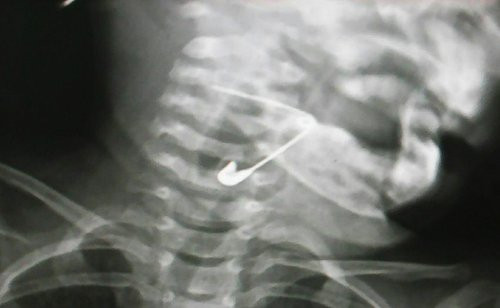

Trưa 23/8, bé gái bị kim băng mắc vào thanh quản được người thân đưa vào Bệnh viện Đa khoa Vĩnh Đức cấp cứu. Kết quả chụp phim X-quang phát hiện cây kim đang mắc ở hạ họng thanh quản bé với đầu nhọn đâm vào phía trong. Các bác sĩ đã nội soi gắp dị vật ra ngoài.

Chiếc kim băng mắc vào hạ họng thanh quản cháu bé 18 tháng tuổi. (Ảnh: Bệnh viện cung cấp)